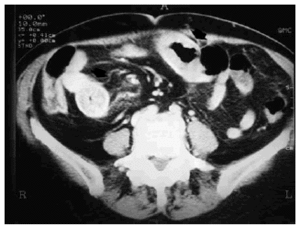

Paciente de 72 años, con antecedentes de hipertensión arterial y fibrilación auricular crónica, hipocoagulada con acenocumarol. Consulta por dolor abdominal cólico en mesogastrio, náuseas y vómitos, presentando en la exploración discreta distensión abdominal y extensa equimosis en la pierna derecha como únicos hallazgos relevantes. El INR inicial fue de 11; tras administrar plasma y vitamina K parenteral el INR se redujo a 1,8. La hemoglobina inicial fue de 11,5 g/dl, con valor valle de 8,2 g/dl a las 24 h. En la tomografía axial computarizada abdominal (figs. 1 y 2) se observó líquido libre perihepático y en pelvis, así como un largo trayecto de asa de intestino delgado con paredes engrosadas (flechas), compatible con hemorragia intestinal intramural. La paciente evolucionó de forma satisfactoria con tratamiento conservador, incluyendo fluidoterapia, analgésicos y aspiración nasogástrica, sin incidencias posteriores. El diagnóstico fue de hemorragia intramural intestinal, sobredosificación por acenocumarol.

Figura 2